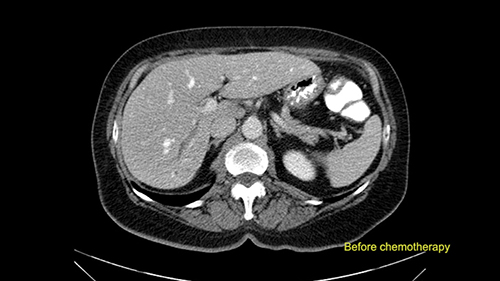

In this patient with multiple synchronous liver metastases that are small in nature, I’m very careful to ensure that I review not just the most recent CT scans but also all of the original CT scans from the time the patient declared with liver metastases so I can locate the original positions of the tumors, I can see the response to chemotherapy, and to ensure that I evaluate all of the areas where the tumors initially were present at the time of surgery to decide whether or not they need to be removed at the time of surgery.

She underwent neo-adjuvant chemotherapy and then had a series of additional investigations and the one that I’m focusing on in more finer detail is an MRI with Primovist and I’ve had the benefit of looking at the report. The main issues are in Segments 5,6, and 7. Three small metastases that remain and the radiologist also comments on the lack of biliary dilatation which was present before; implying that the intrabiliary metastasis somewhere at the origin of the Segment 7 duct, has regressed or been adequately well treated with chemotherapy. That’s probably where the difficult decision making comes in the OR. So from an oncologic point of view, I would plan for a right hepatic lobectomy. The rationale would be that this would include the more peripheral Segment 5, 6, 7 metastases that are obvious but also would take care of the presumed Segment 7 intrabiliary metastasis that does not actually visualize on any of the scans but is assumed to be there with evidence of the duct dilatation which then resolved. One could argue whether we should preserve liver and ignore that duct dilatation that was there before but I think my own preference would be to resect the right lobe and that would certainly include any residual disease in that Segment 7 bile duct and moreover, coming back to do a completion right hepatic lobectomy would be difficult particularly around the porta where this metastasis is presumably still there and even if its quite small.

I am Professor Jacques Belghiti, hepatobiliary surgeon. I practiced at Beaujon Hospital at Paris Diderot University Paris 7. I will discuss the case of a 65-year old patient who has hepatic metastases from a colon cancer operated on one year before. Two particular points with this patient: She has had a cholecystectomy at the time of colectomy, and at the discovery of the lesions in which there were 3, all located in the right liver, we noted the existence of biliary dilatation. This biliary tract dilatation could have been a consequence of the cholecystectomy, or due to a particular form of metastasis with biliary infiltration; and my impression is that the second hypothesis should be supported for two reasons. The first reason is that on the initial CT scan, we had a feeling that the biliary tract dilatation was associated with a small tumor/lesion. The second reason is that the dilatation decreased after several courses of chemotherapy. I don’t know how many courses of chemotherapy she had, but in any case, there exists some lesions of the hepatic parenchyma, with steatosis that may have been a consequence of this chemotherapy. After several courses of chemotherapy, we see at least 2 lesions persisting in the posterior sector of the right liver and dilatation of the biliary tracts. There might be another lesion at the junction of Sg 5 and 8. So this patient should now be operated on since we are faced with lesions that persisted after chemotherapy.